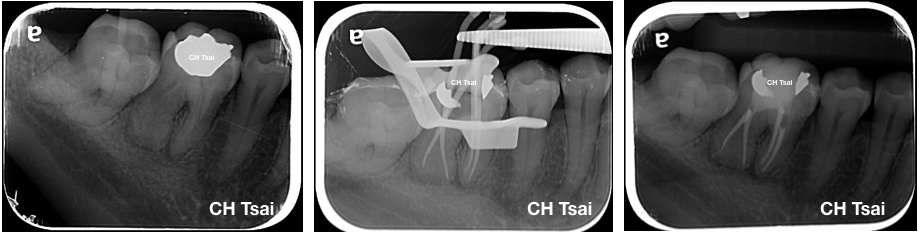

病人因牙髓炎疼痛求診,在治療前的根尖片可以發現右下第一大臼齒遠心根管鈣化;根管的鈣化是牙髓遇到外傷或蛀牙保護的機制,需要有經驗的專科醫師搭配顯微鏡及其他設備的治療,來提高根管治療成功的機會。

在一開始的X-ray中,可見遠心牙根根管極度鈣化,經專科醫師進行顯微根管及超音波療程後,順利完成治療。